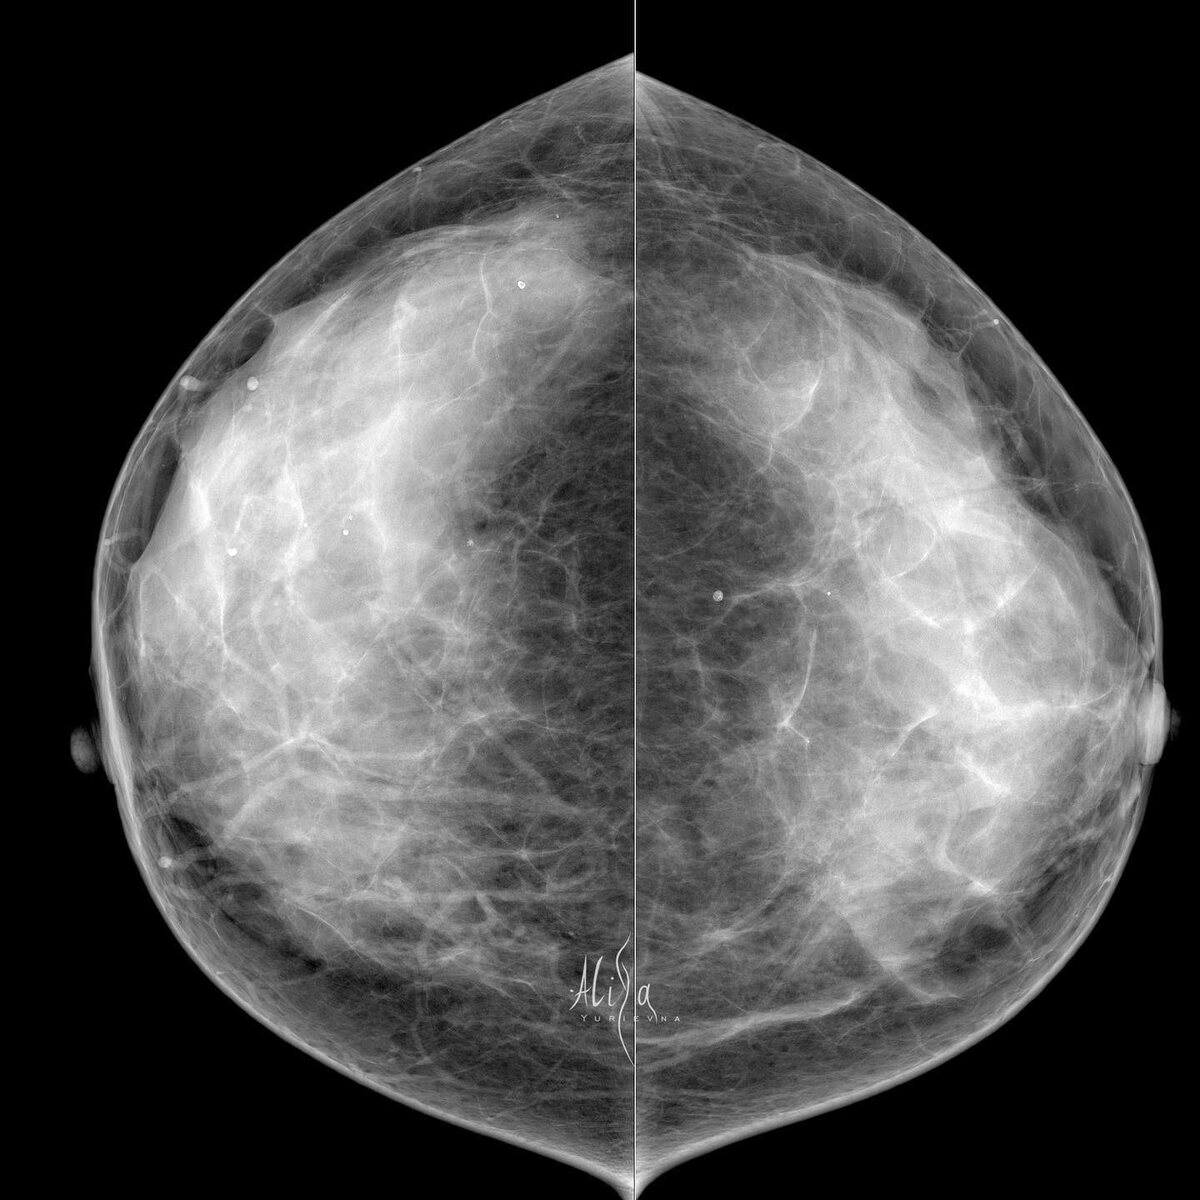

Кейс. Пациентка 38 лет

Плотный рентгенологический фон. Именно он порой не дает нам увидеть на маммограмме образования. Именно он повышает риск развития карциномы молочной железы. Именно при такой структуре железы обязательно назначается узи, которому плотный фон не помеха. Помощниками нам здесь, конечно, являются измененные лимфатические узлы справа. Видя их, ищем причину в молочной железе. И видим «выбухание» переднего контура паренхимы в косой проекции. Именно там и сидит виновник метастазов в аксиллярной зоне. Трипл, конечно же. Инвазивная карцинома G3, ИГХ: ER( 0 ) PR( 0 ) HER2neu ( 0 ) Кi67 30-40%

Плотный рентгенологический фон. Именно он порой не дает нам увидеть на маммограмме образования. Именно он повышает риск развития карциномы молочной железы. Именно при такой структуре железы обязательно назначается узи, которому плотный фон не помеха.

Помощниками нам здесь, конечно, являются измененные лимфатические узлы справа. Видя их, ищем причину в молочной железе. И видим «выбухание» переднего контура паренхимы в косой проекции. Именно там и сидит виновник метастазов в аксиллярной зоне.